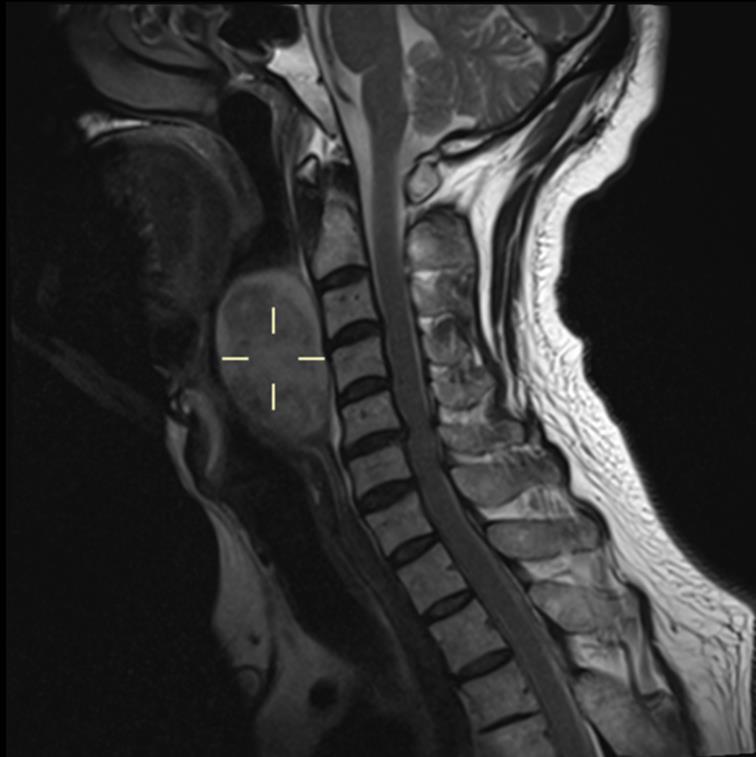

50岁的万先生(化名)在一次颈椎检查时,被偶然发现咽后壁有一个巨大肿块。怀着忐忑的心情,他慕名来到仁济医院耳鼻咽喉科主任医师刘君的诊室。刘君仔细解读影像,发现肿块严重压迫正常组织,随时可能引发功能障碍,且存在恶变风险,手术切除风险虽高,但势在必行。

进一步的鼻咽喉镜与增强CT检查显示,肿块体积大,几乎堵塞喉咽腔,其侧翼更是紧邻颈部大血管。病灶位置特殊,使得常规全身麻醉下的声门暴露变得异常困难,必须进行气管切开,这无疑会给患者带来额外的创伤。